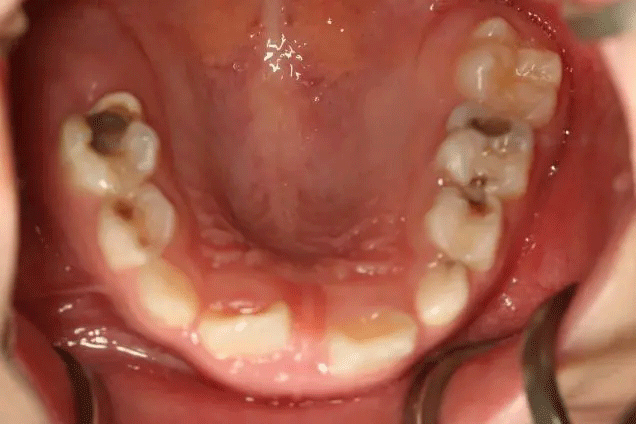

很多家長對乳牙蛀牙不以為然

孩子1歲開始已經出現齲齒

但是媽媽2年后才帶孩子就診

這時,孩子已經斷斷續續疼了3年

有些牙齒都已經爛得很嚴重了

甚至牙齒幾乎都爛光僅剩下牙根